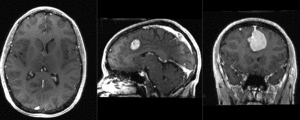

Registration Results

unregistered

after affine alignment using the General (BRAINS) registration module

unregistered after affine alignment using the General (BRAINS) registration module]